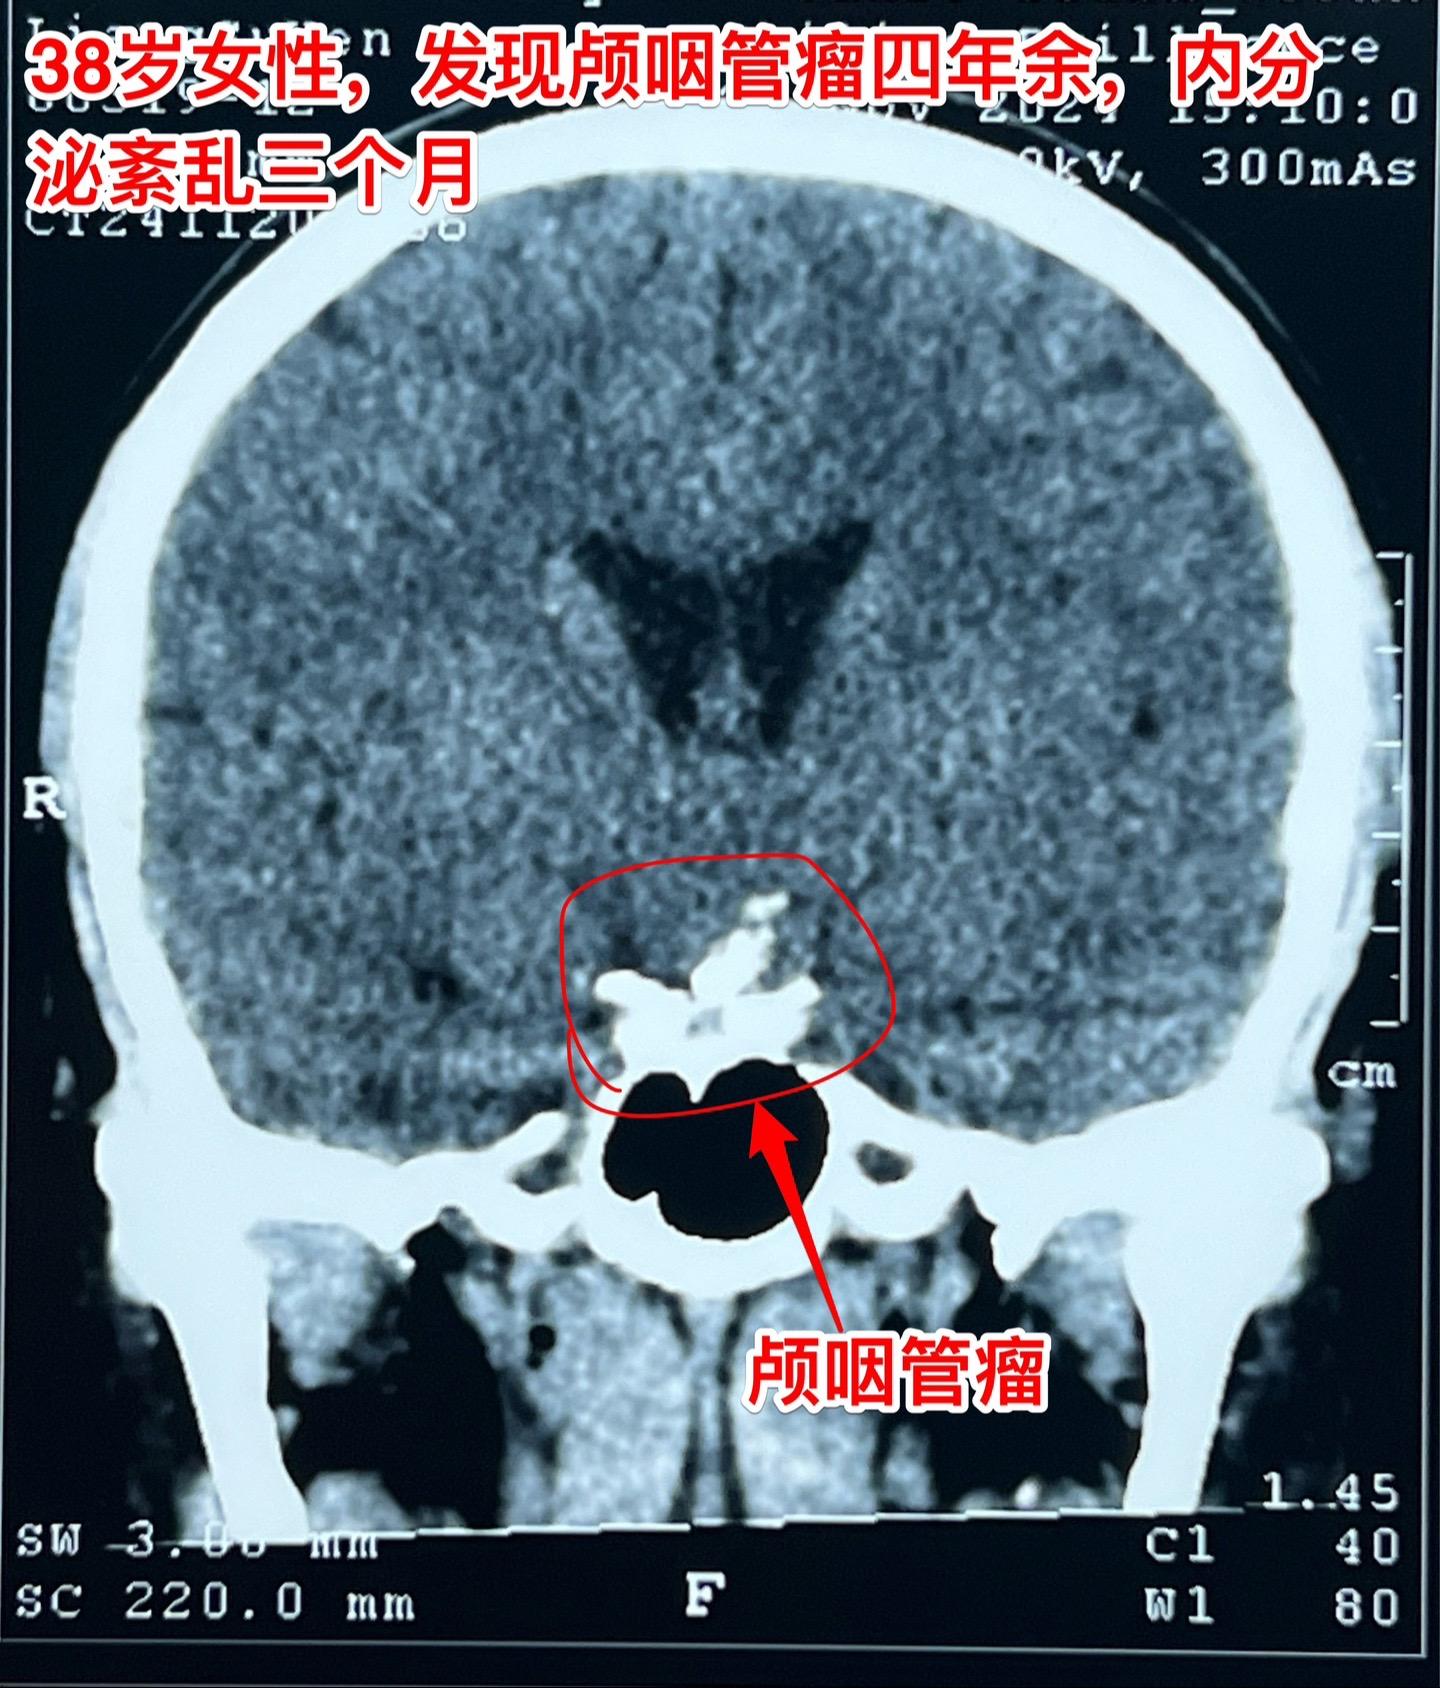

颅咽管瘤等待四年多才作手术,是否合适?偶然发现的颅咽管瘤,病人几乎没有什么症状,是不是要尽早作手术呢?颅咽管瘤的治疗一直是神经外科界的难题,手术时机选择也是一个难点。 今天以一个实际的病人来说明。 38岁的绍兴女性,在2020年初经体检发现了颅咽管瘤,当时几乎没有什么症状,曾经通过咨询过我,之后一直在观察。患者在2014年左右生育孩子,发现颅咽管瘤后内分泌系统都很正常。 直到今年夏天患者发现内分泌系统紊乱了,复查磁共振显示肿瘤体积增大了。她这才下定决心找我